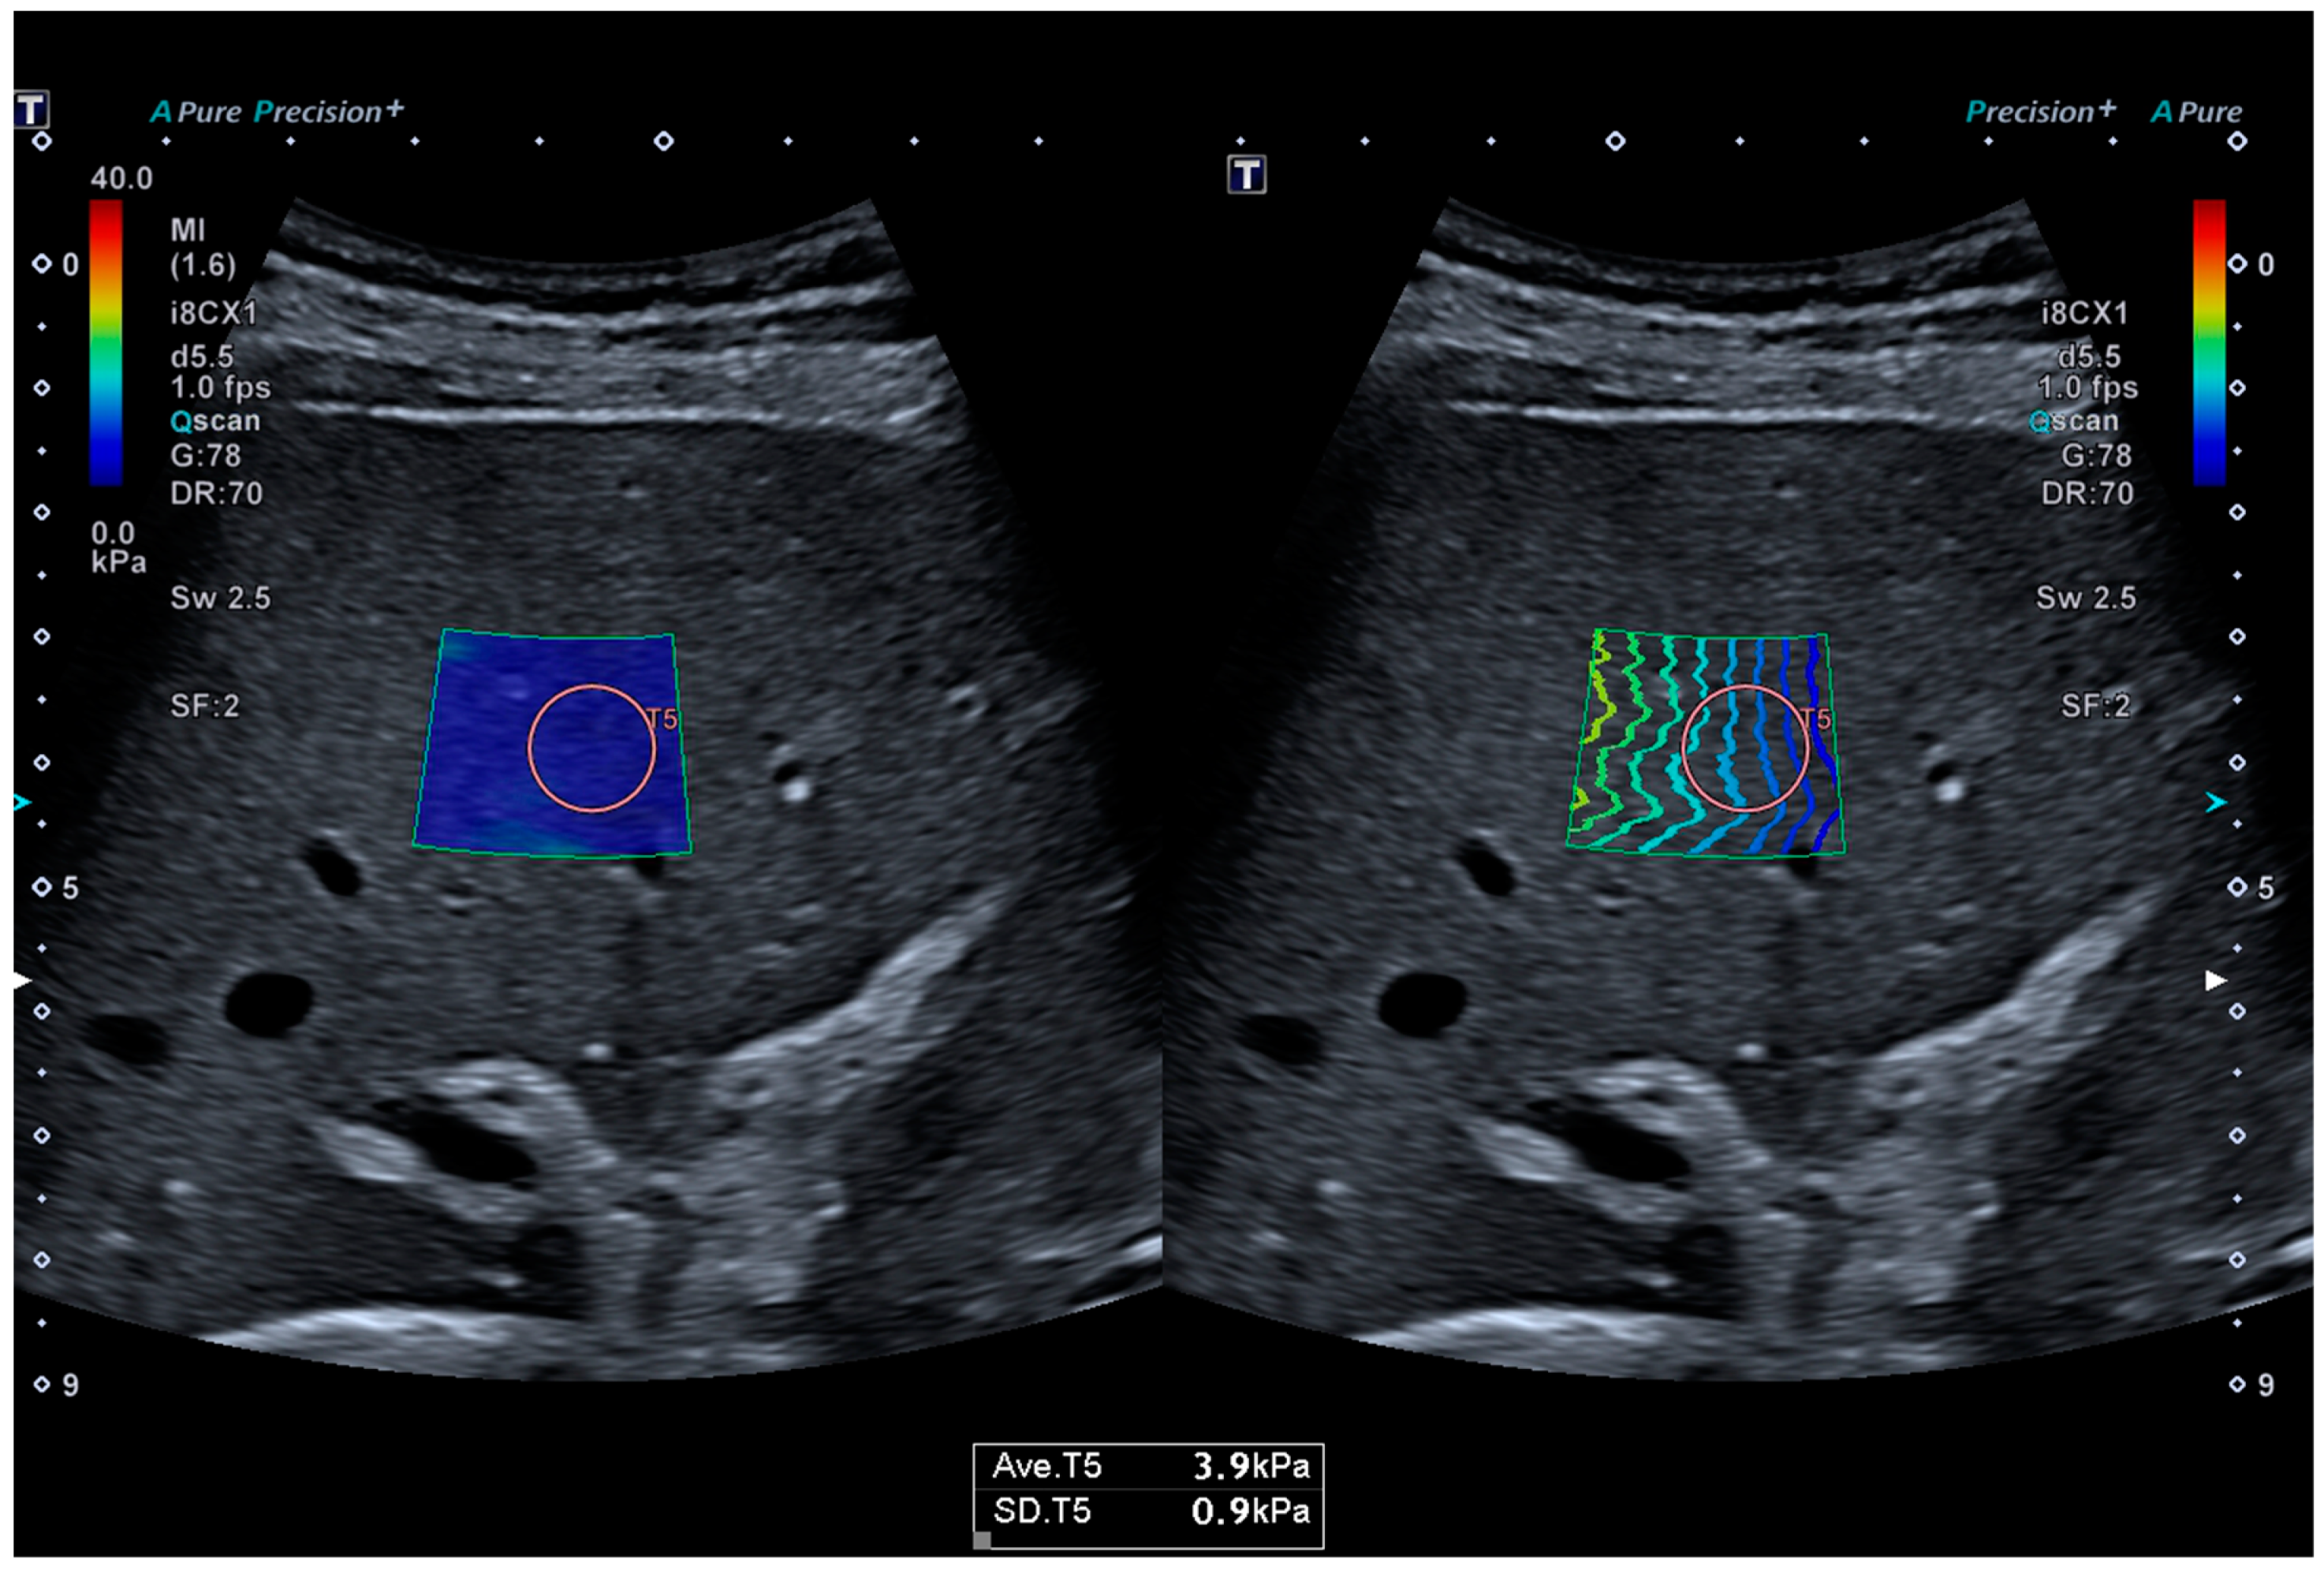

2.1. 2D-SWE and SWD

| 2D-SWE | 1.42 m/S, Range 1.14–1.83 m/S |

| 6 kPa, Range 3.9–10.2 kPa | |

| SWD | 14.2 m/S/kHz, Range 10.3–18.5 m/S/kHz |